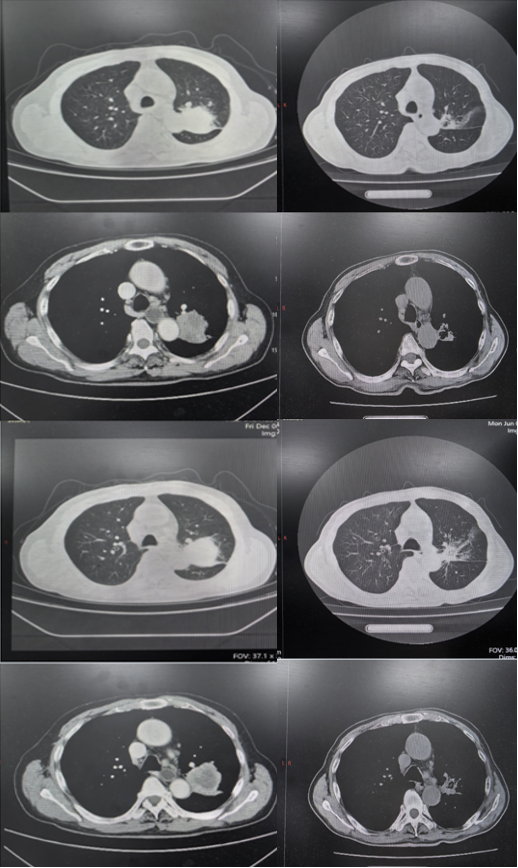

2025-04-26 用药5周期后,胸部CT结果如下所示,疗效评估为PR

图8 2024-12-6(左)对比2025-04-26(右)胸部CT

2025-6-16 用药7周期后,胸部CT结果如下所示,疗效评估为PR

图9 2024-12-6(左)对比2025-06-16(右)胸部CT

截止最新随访时间(2025-09-12),该患者持续PR,目前仍在接受“依沃西单抗联合化疗”方案治疗。